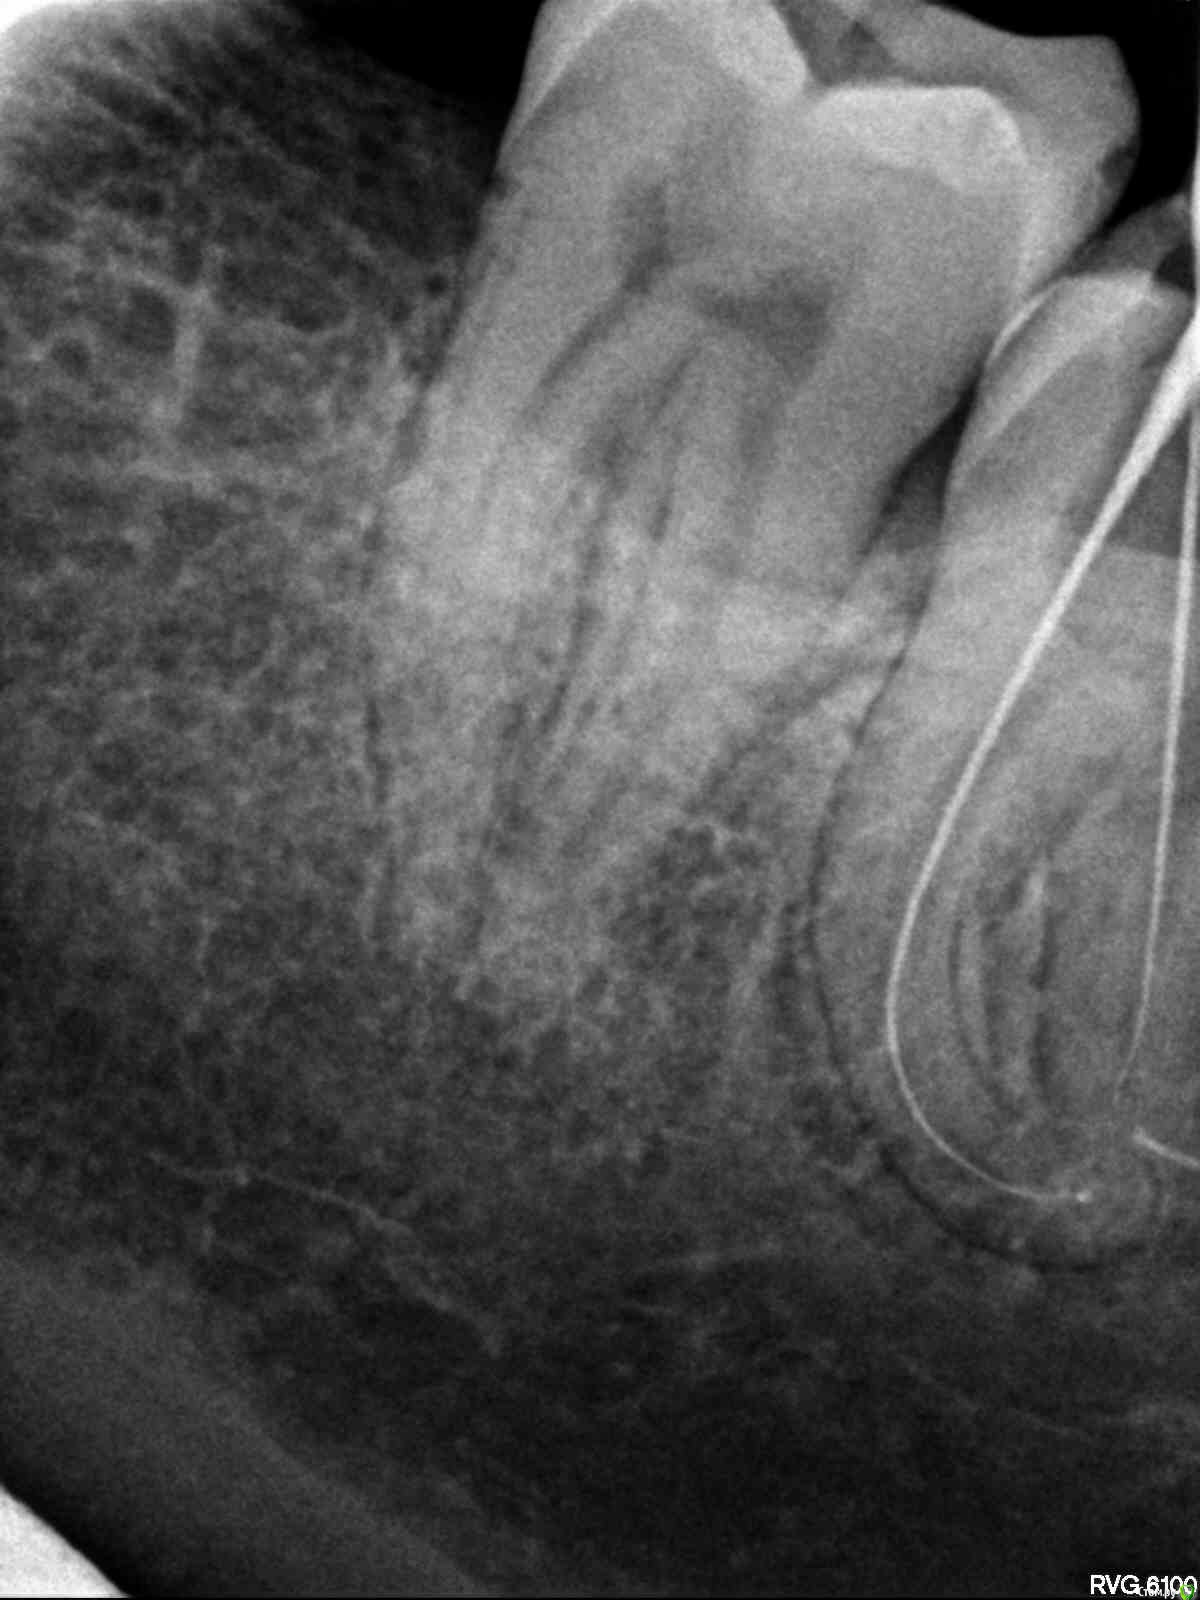

Витторио Орлионе Опубликовано 24 июня, 2015 Поделиться Опубликовано 24 июня, 2015 Уважаемые коллеги, очень нужен ваш мудрый совет. Пациентка обратилась в клинику 23.06 с жалобами на пульсирующие боли в области нижней челюсти слева. На окклюзионной поверхности зуба 3.8 глубокая кариозная полость не сообщающаяся с полостью зуба. Зондирование болезненно, температурная проба положительная, перкуссия слабо болезненна. Пациентка хотела сохранить зуб. Поэтому анестезия, некрэктомия, раскрытие и формирование полости, обработка ручными и mtwo файлами, мыл гипохлоритом. Итог: патенси нет, обломок инструмента, пульпевит №3, септопак. Явка 25.06. Если лечить то:Сообщать ли пациентке об обломке?Какую тактику выбрать (вести на каласепте или отмыть и запломбировать, стоит ли пытаться достать)?Чем пломбировать каналы (гуттаперча или резорцин)? Если удалять то?Как обосновать пациентке смену лечения на удаление?Разделять корни или нет? Ссылка на комментарий

Витторио Орлионе Опубликовано 24 июня, 2015 Автор Поделиться Опубликовано 24 июня, 2015 да, первый эндокосяк, пульпу убрал и пару раз промыл, полом полез 10.02 mtwo и устроил фото сессию.В этот раз без коффера работал, далеко очень, вот и не стал использовать. Ссылка на комментарий

Ico Опубликовано 24 июня, 2015 Поделиться Опубликовано 24 июня, 2015 (изменено) то есть можно обойтись и без каласепта?В вашем случае необходими выполнить основной мед-мех протокол очистки,до обломка,потом,доплнительно ирригация с активацией.Если нет болевой периодонтитной симптоматики,то паковать надо сразу,т.к есть шанс протолкнуть силер к фрагменту и сделать паковку более герметичной без пустот.Если же будете с кальцием делать,то обязательно убедитесь,что она плотно распределена в апекальной части канала,иначе эффекта от нее не будет. Изменено 24 июня, 2015 пользователем Ico Ссылка на комментарий

Гарриевич Опубликовано 24 июня, 2015 Поделиться Опубликовано 24 июня, 2015 Как есть так и подайте, зуб 8-ой по ААЭ это запредельная сложность, сломать там инструмент это конечно не приятно, но предсказуемоКак сказал Ico, мойте, мойте, мойте и пакуйте. Резорцин ни к чемуЕсли сломали 10ку то можете в принципе полчаса потратить и постараться его обойти. Главное не пытайтесь это сделать ротари Ссылка на комментарий